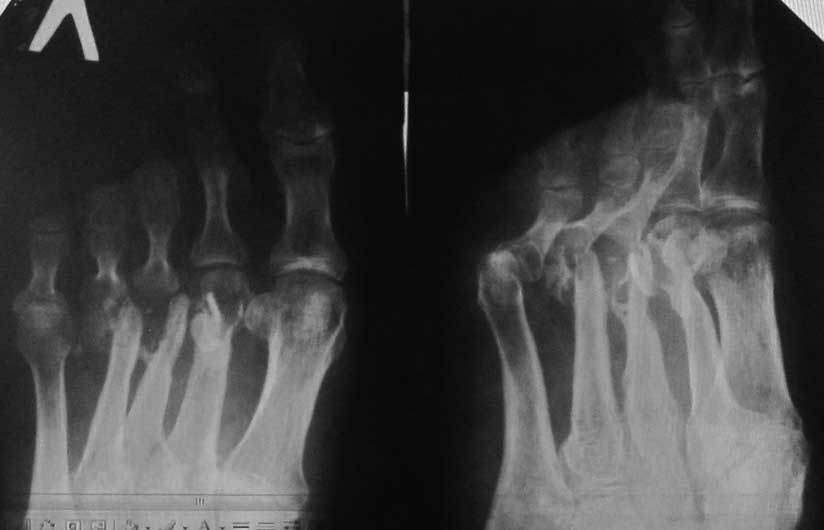

[Ortho] Хронический остеомиелит плюсневых костей

Больной 45 лет, мужчина. Оперирован спицами в мае 2013 года в

Таджикистане по поводу открытых переломов 2-4 плюсневых костей. Спицы

были удалены со слов больного через 2 недели, после чего он был выписан

на амб. долечивание, приступил к дозированной нагрузке. В сентябре 2013

года открылся свищевой ход на тыле стопы в 3-м межплюсневом промежутке.

Больной лечился самостоятельно различными антибиотиками. Рассматривается

секвестрнекрэктомия головок и части диафизов 2-4 плюсневых костей,

проточно-промывное дренирование+спейсер с

ванкомицином (или без спейсера), а затем в холодном периоде костная

аутопластика. Возможно после секвестрнекрэктомии появится избыточная

подвижность 2-4 пальцев, чем и как посоветуете фиксировать??